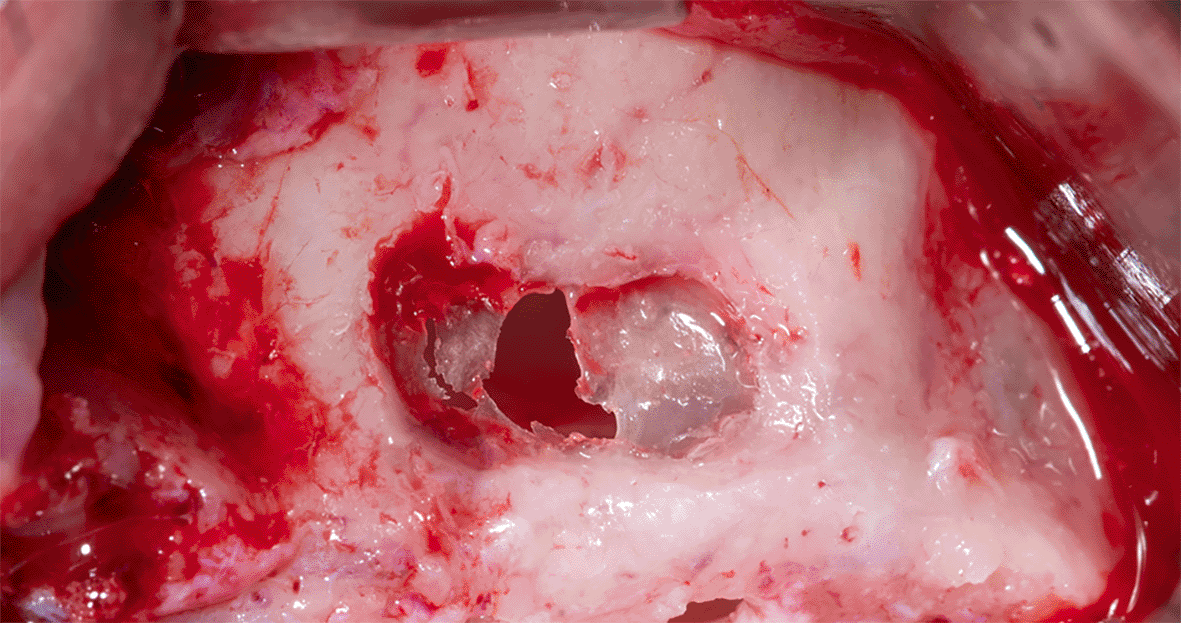

The membrane lifted from the inner sinus walls. Once the final intervention window is prepared ( Figure 4), we prepare the absorbable collagen membrane (Jason® membrane, Botiss, Germany) using the modified design performed by the researcher as it was used in this study for the first time ( Figure 5), where the membrane is measured and divided imaginarily into three parts as follows:

72a8e8c6-ed30-422d-8d84-4a8b8f46f6f2_figure4.gif

Figure 4. The final window after lifting the schneiderian membrane.